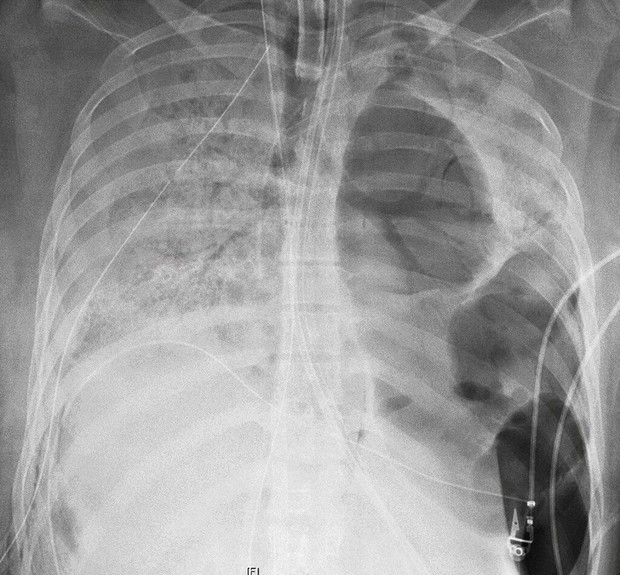

Coronavirus Survivor In Us Receives Double Lung Transplant The Mainichi

Coronavirus Survivor In Us Receives Double Lung Transplant The Mainichi from cdn.mainichi.jp